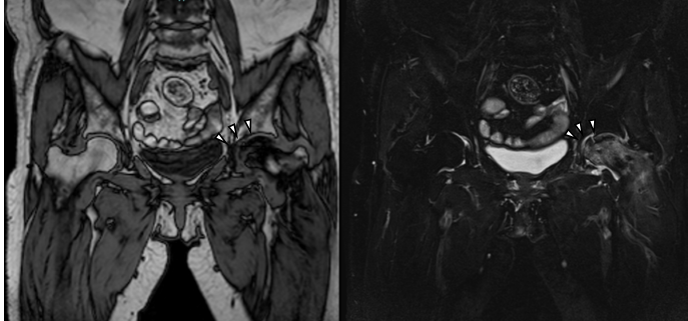

An 80-year-old woman with terminal lung adenocarcinoma developed left hip pain in February of year X-1. At her initial visit to our clinic in May, radiographs showed collapse of the left femoral head (Fig. 1). Magnetic resonance imaging (MRI) scans revealed a SIF (Fig. 2).

Figure 1: Radiograph at the first visit showing a subchondral fracture line in the left femoral head.

Figure 2: Magnetic resonance imaging at the initial visit. The T1-weighted image (left) shows a low-signal area in the femoral head, and the short tau inversion recovery image (right) shows a corresponding high-signal area, indicating a subchondral insufficiency fracture (arrowheads).